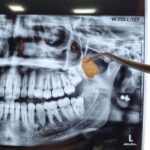

در بعضی موارد مراجعه دیرهنگام فرد برای کاشت دندان (ایمپلنت) یا وجود کیست و تومورهای دهانی منجر به از بین رفتن فضای مناسب و کم شدن قطر و ارتفاع استخوان فک میشود که در این حالت، دندانپزشک قبل یا همزمان با جایگذاری فیکسچر، با استفاده از پودر و بلاک استخوانی و ممبرین (بایومتریالها) استخوان را بازسازی کرده تا شرایط مناسب برای قرارگیری ایمپلنت مهیا گردد. در این مواقع طول درمان بیمار (آماده شدن استخوان برای جایگذاری ایمپلنت) بسته به شرایط بیمار از ۳ تا ۶ ماه طول میکشد و دندانپزشک به کمک عکسهای رادیوگرافی میتواند روند درمان را دنبال کند و بهترین زمان را برای کاشت ایمپلنت تشخیص دهد.